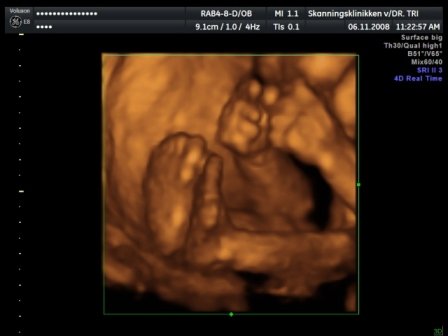

kaptunk félórás dvd-t a vizsgálatról, kétoldalas leírást a bébiről, 3 fekete-fehér képet és egy színeset kinyomtatva, és 23-at egy másik dvd-n:D tök rendes volt a csaj... de a kis drágám nagyon dugdossa az arcocskáját.. mindent megmutat, de az arca az magánügy úgy gondolja :D azért elég makacsak voltunk úgyhogy nagy nehezen sikerált egy profil :D azt mondta a dokinő hogy nagyon nagyon aktív bébi :D és teljes bizonysággal kistökös :D:D:D Kép bébi 4D Kép a kis tökös Kép kezek-lábak